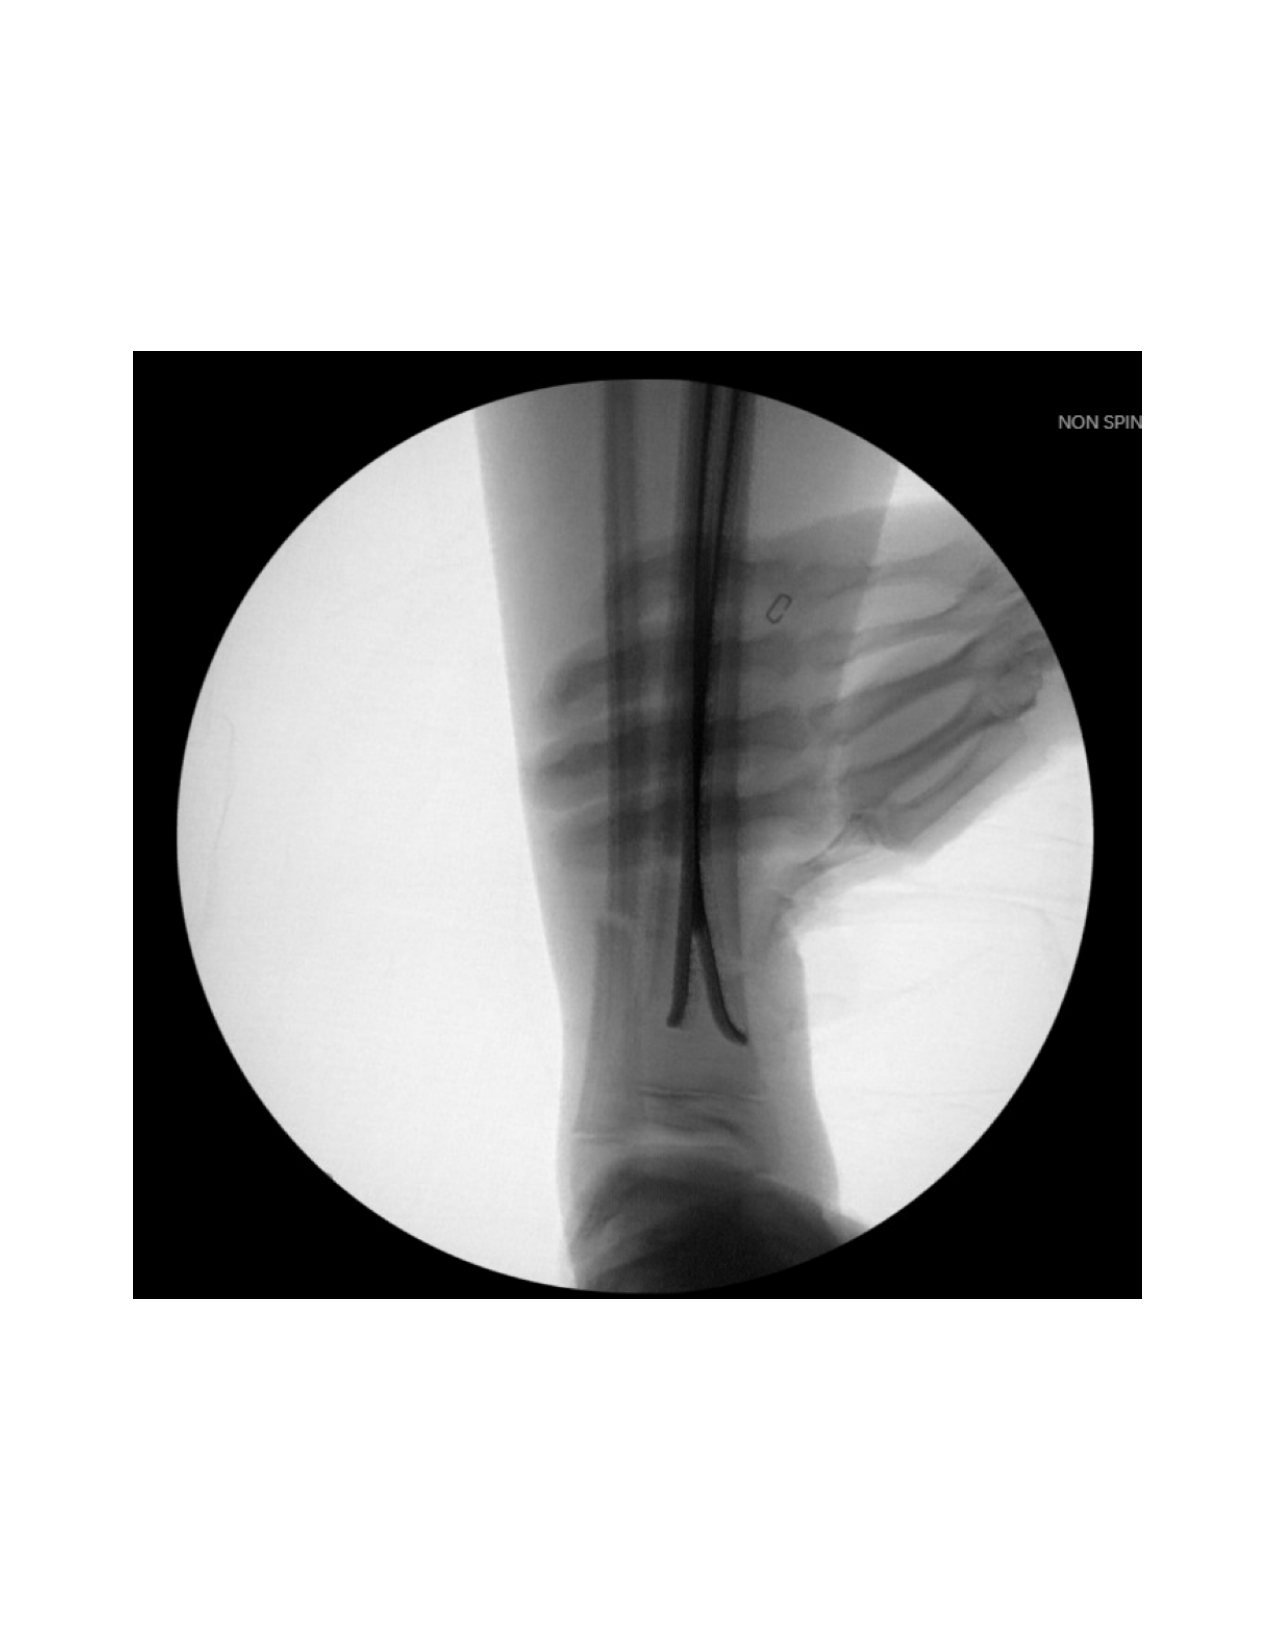

Next, the fracture is manually reduced and both nails are gently advanced past the fracture site by mallet. The curvature of the nails and their tips assists in reducing and stabilizing the fracture, inserted shy of the growth plate. Nail positioning is confirmed by fluoroscopy (Figure 5).

If displacement occurs after insertion, additional nail contouring may be necessary. To correct valgus angulation, the lateral nail can be rotated 180o medially. For procurvatum angulation, both nail tips are rotated 90o anteriorly without altering the medial and lateral orientations. For recurvatum deformity, both nail tips are directed posteriorly. Once a satisfactory reduction is achieved, the nails are hammered distally, preserving the distal physis (Figure 6).

The fracture site is then reassessed under fluoroscopy to confirm maintained reduction. (Figure 8 and Figure 9) Wounds are irrigated and closed in two layers, followed by sterile dressing and short leg splint application.